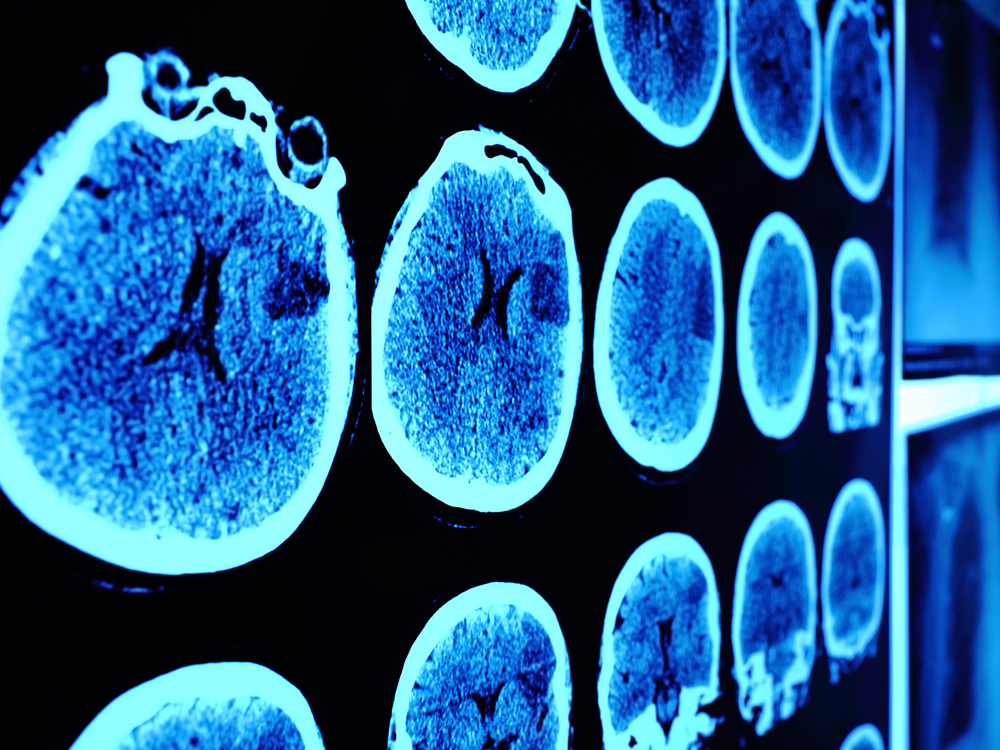

In a new study, some patients who had an aggressive type of brain cancer called glioblastoma and who received a genetically modified poliovirus lived much longer than typical for these patients.

People with glioblastoma — the most common type of cancerous brain tumor in adults — typically live less than 20 months after their diagnosis, the researchers said. And patients with a recurrence of this cancer (meaning cancer appeared to go away and then came back) typically survive less than 12 months.